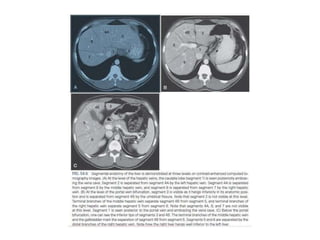

• The Couinaudclassification of liver anatomy divides the liver into eight functionally indepedent segments. Each segment has its own vascular inflow, outflow and biliary drainage. In the centre of each segment there is a branch of the portal vein, hepatic artery and bile duct. In the periphery of each segment there is vascular outflow through the hepatic veins. The liver is divided in three vertical planes: • The plane of the right hepatic vein divides the right lobe into anterior and posterior segments. • The plane of the middle hepatic vein divides the liver into right and left lobes or right and left hemiliver. This plane runs from the inferior vena cava to the gallbladder fossa. • The umbilic plane runs from the falciform ligament to the inferior vena cava and divides the left lobe into a medial part, which is segment IV and a lateral part formed by segment II and III. This division is the only vertically oriented plane that is not defined by a hepatic vein

• How toseparate liver segments on cross sectional imaging • Left liver: lateral(II/III) vs medial segment (IVA/B) Extrapolate a line along the falciform ligament superiorly to the confluence of the left and middle hepatic veins at the IVC (blue line). Left vs Right liver: IVA/B vs V/VIII Extrapolate a line from the gallbladder fossa superiorly along the middle hepatic vein to the IVC (red line). Right liver: anterior (V/VIII) vs posterior segment (VI/VII) Extrapolate a line along the right hepatic vein from the IVC inferiorly to the lateral liver margin (green line).